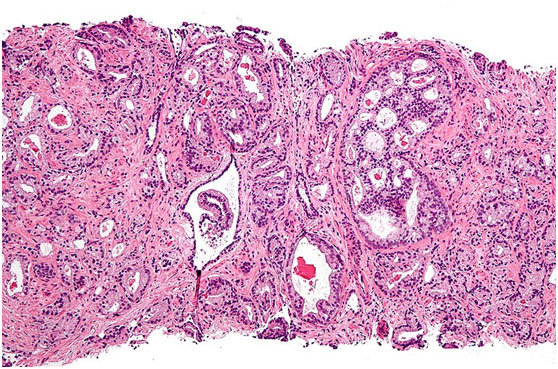

顯微照片顯示前列腺腺泡腺癌(前列腺癌的最常見形式)圖片來(lái)源:維基百科